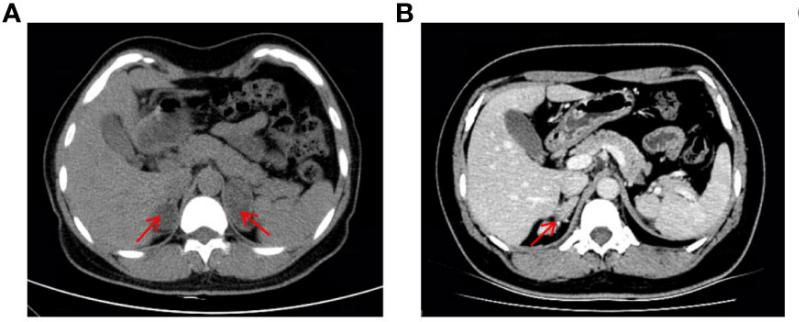

¸Ã»¼ÕßÊÇÒ»Ãû37ËêµÄÅ®ÐÔ£¨ºËÐÍΪ46£¬XX£©£¬Í¯Äêʱ±£´æÉú³¤¼ÓËÙ£¬ÇÒ»éºóһֱδÓÐÉí¡£2019ÄêÒòÒÉÕïË«²àÉöÉÏÏÙÖ×ÁöÈëÔº£¨Í¼1A£©£¬Ç°ºó¾ÙÐÐÁËÁ½´ÎÉöÉÏÏÙÇгýÊõ¡£2022Ä꣬»¼ÕßÓÉÓÚÔ¾²»¹æÔò±»ÊÕÈëÄÚÉøÍ¸¿Æ£¬CTÏÔʾÓÒÉöÉÏÏÙÆ¤ÖÊÔöÉú¸´·¢£¨Í¼1B£©£¬Ìå¸ñ¼ì²éÏÔʾ¸Ã»¼Õ߯¤·ôÉ«ËØÀä¾²£¬Ã沿ÓÐðî´¯ºÍ÷×룬·ºÆðÄÐÐÔ»¯ÌåÕ÷£¬Éú»¯¼ì²éÌáÐѵͼØÐÔ¸ßѪѹ£¬¸ßÐÛѪ֢¡£¾ùÌáÐÑ11¦Â-OHDÕï¶Ï¡£

ͼ1 »¼Õ߸¹²¿CTÓ°Ïñ